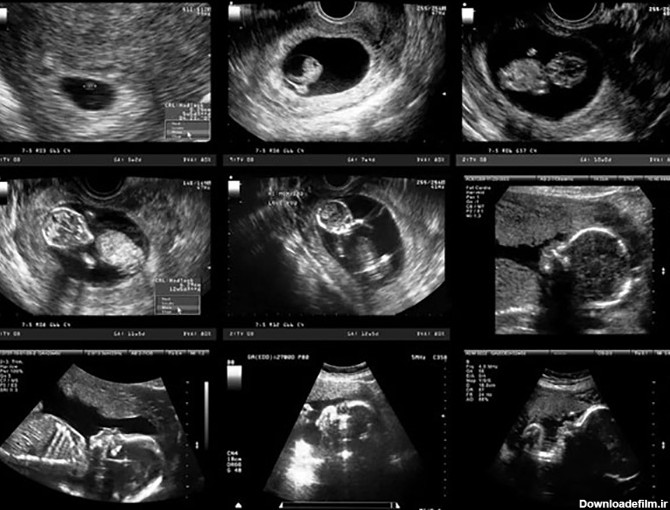

مراحل رشد جنین ، در این مدت زمان تشکیل مغز و قلب و استخوان ها و رگ های خونی کودک است در این بازه جنسیت و رنگ مو های جنین مشخص میشود.

جنین در کل دوران بارداری بوسیله جفت و بند ناف تغذیه می کند. جنین در رحم مادر نسبت به صداهای اطراف مادر و نور واکنش نشان می دهد. حالات مختلف جنین هفته به هفته در بارداری را با سونوگرافی میتوان مشاهده کرد.

بارداری هفته به هفته،هفته به هفته بارداری،عکس جنین در هفته های مختلف،تقویم بارداری،دوران بارداری هفته به هفته،بارداری هفته به هفته با عکس،بارداری هفته،بارداری هفته به هفته همراه با عکس،هفته به هفته با بارداری،عکس بارداری هفته به هفته،تصاویر جنین در هفته های مختلف بارداری،اندازه جنین در هفته های مختلف،جنین در هفته های مختلف،هفته های بارداری با تصویر